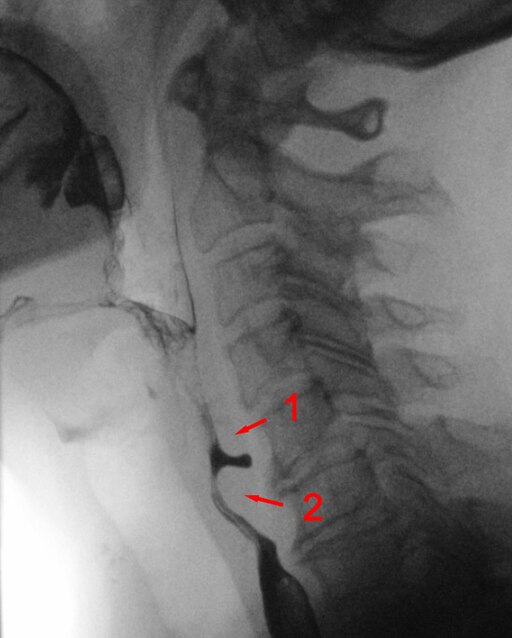

Zenker-Divertikel

DefinitionZenker-Divertikel

Das Zenker-Divertikel ist eine pulsionsbedingte Ausstülpung der Schleimhaut durch eine muskelschwache Zone der Pharynxwand. Es entsteht typischerweise im Killian-Dreieck (Schwachstelle zwischen Pars obliqua und Pars fundiformis des M. cricopharyngeus) im dorsalen Hypopharynx.

Obwohl es klinisch oft zu den Ösophagusdivertikeln gezählt wird, liegt der anatomische Ursprung im Hypopharynx.

Zenker2.jpg von Hellerhoff, CC BY-SA 3.0, via Wikimedia Commons

Männer sind häufiger betroffen, der Altersgipfel liegt zwischen dem 50. und 70. Lebensjahr.

Ursache ist eine unzureichende Relaxation des M. cricopharyngeus (oberer Ösophagussphinkter) beim Schluckakt. Dies führt zu einer Druckerhöhung im Hypopharynx. Die Folge ist eine pulsionsbedingte Ausstülpung der Schleimhaut nach dorsal.